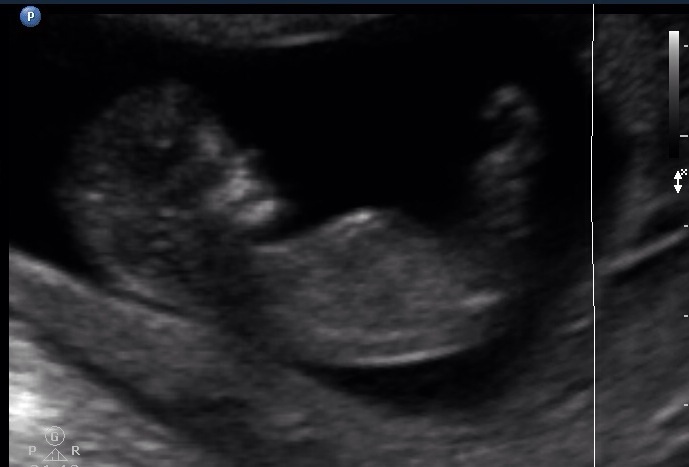

Hi guys!!! Desperately hoping for a little boy and hoping you can guess on these two pics. Thank you!!!

I'm pretty certain that's a little girl. Sorry, I know you were hoping for blue.

I can't tell were the nub is :suprise:

Guessing girl, sorry!

I don't see any clear nub... Slight girl lean from pic 2 but still close to 50/50. What did you see during the live scan?

I'm sorry, I have to guess girl here. Nubs are definitely not 100% though...plenty of very girly nubs have ended up being boys and vice versa. There was one woman on here who got pages of only girl nub guesses and her baby ended up being a boy at the 20 week scan. Don't give up hope, congrats on a lovely baby.

I was going to say girl at first but zooming in there is something on top of that girly nub which could possibly make it a stacked nub = boy. im going 50/50 but dont give up hope just yet